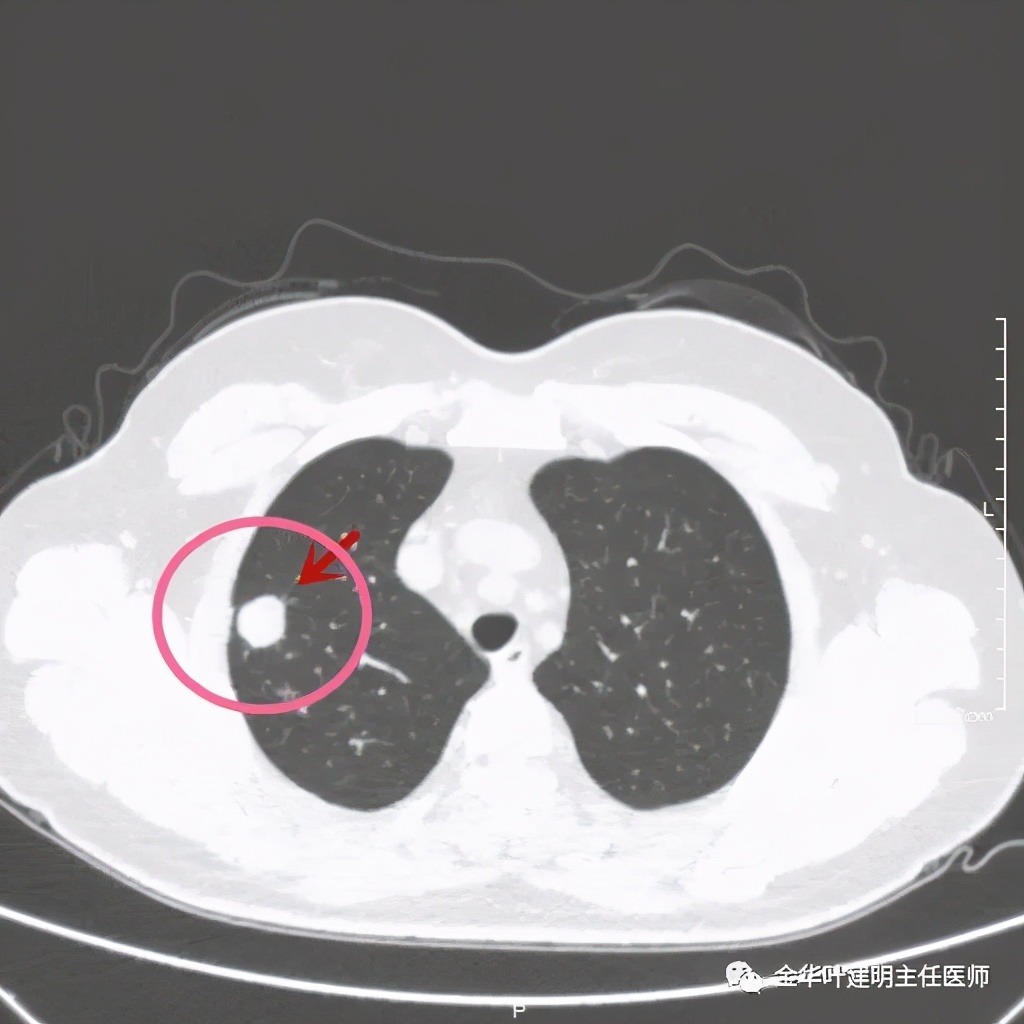

总体感觉病灶较大,但边缘过于光滑,缺乏收缩力,没有毛刺征、分叶征、胸膜凹陷征;旁边却有多发微小实性或似磨玻璃结节,周围不清爽。让人感觉非肿瘤性质,炎性可能性大些,比如结核等。那么纵隔窗又是如何呢?我们选两个层面来看:

粉色箭头示病灶边缘光滑,没有毛刺,距胸膜近,但无牵拉凹陷。桔色箭头示病灶内有局部强化(血管?)

上图粉色箭头示病灶一侧非常靠边的地方居然有个小空泡:是结节内坏死形成的吗?这样大小的不符合呀,而且太靠边上了;是扩张的支气管吗?有可能,若病灶是肺癌,应该有破坏才比较符合,我们看它空泡比较光滑,没有堵塞或破坏。就是说,感觉与恶性是不太符合的。所以它应该是个良性的病灶!当然直径达2厘米的实性病灶,又这么靠外周部位,楔切非常简单,既可去除病灶,又可明确诊断,手术是可以考虑的。下面是术后病理结果: